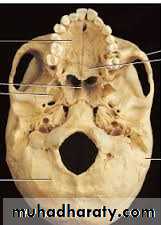

e- Floor : formed by 4 bones : frontal ,parietal , temporal, and sphenoid forming pterion which is thinnest part of the lateral wall of the skull where the anteroinferior corner of the parietal bone articulates with the greater wing of the sphenoid . Clinically , the pterion is an important area because it overlies the anterior division of the middle meningeal artery and vein .

The bone of calvarium is thinnest in the temporal fossa. Strong blows to the side head may cause a depressed fracture, in which a fragment of bone is depressed inward to compress or injure the brain. At the pterion , the middle meningeal artery is easily ruptured following such an injury CAUSING EXTRA DURAL HEMATOMA that compress the brain and could be fatal if untreated.Benign masseteric hypertrophy is a relatively uncommon condition that can occur unilaterally or bilaterally . pain may be a symptom, but most frequently a clinician is consulted for cosmetic reasons . although it is tempting to point to malocclusion, bruxism , clenching or based on awareness of the condition, clinical and radiographic finding, and exclusion of more serious pathology such as benign and malignant parotid disease